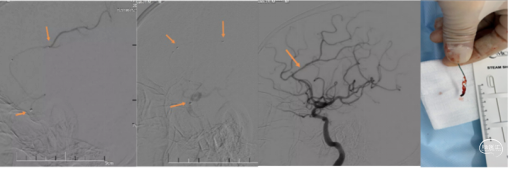

右侧颈总造影发现,右侧颈内动脉起始处有斑块,两处充盈缺损。

使用泥鳅导丝试探,很幸运,毫不费劲就通过了狭窄处,因此考虑此处未完全闭塞,而且远处的栓子可能就来源于此处。将5F125cm Navien沿着泥鳅导丝轻松通过狭窄处,进行抽吸清理颈内动脉可能滞留血栓。跟进8F导引导管通过狭窄部位起到支撑作用。

上干和大脑前为功能区血管,应该开通:

先开通大脑中M2段。支架导管到位,确认远端通畅,尼科医疗的Reco支架3X20mm到位,5F Navien跟到M1,一边抽吸一边拉栓,一把拉通。

注意:应该微导管半收拢支架钳夹血栓,缓慢回拉,防止牵拉血管支撑组织导致脑出血。

再开通大脑前A2段,同样尼科医疗的Reco支架3X20mm到位,5F Navien 跟进A1,半收拢支架,一边抽吸一边拉栓,一把拉通。

回头处理颈内动脉起始部。常规保护伞4-6mm保护下行4-6mm球囊扩张,并自膨支架7-9-40mm植入。